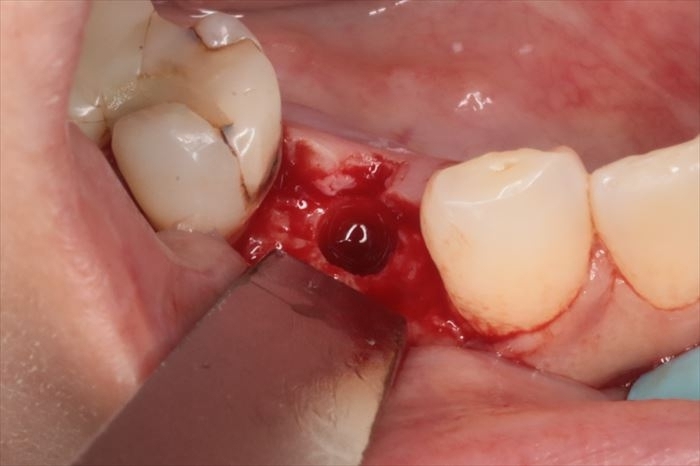

粘膜を剥離して骨の位置を確認します。

骨内にジルコニアインプラントの埋入を終えました。

ジルコニアインプラントは、いわゆるアバットメントまでが一体となったワンピースインプラントですので

適切な埋入位置・埋入深度・埋入トルクが要求されるため、術者にとっては難易度が高い治療と言えます。

最終的にかぶせる歯冠形態を常に意識しながら埋入することが重要です。

埋入後に頬側骨の裂開は見られませんでしたが、矢印の陥凹部分に骨移植材を填入して

骨増生処置(GBR)を行います。